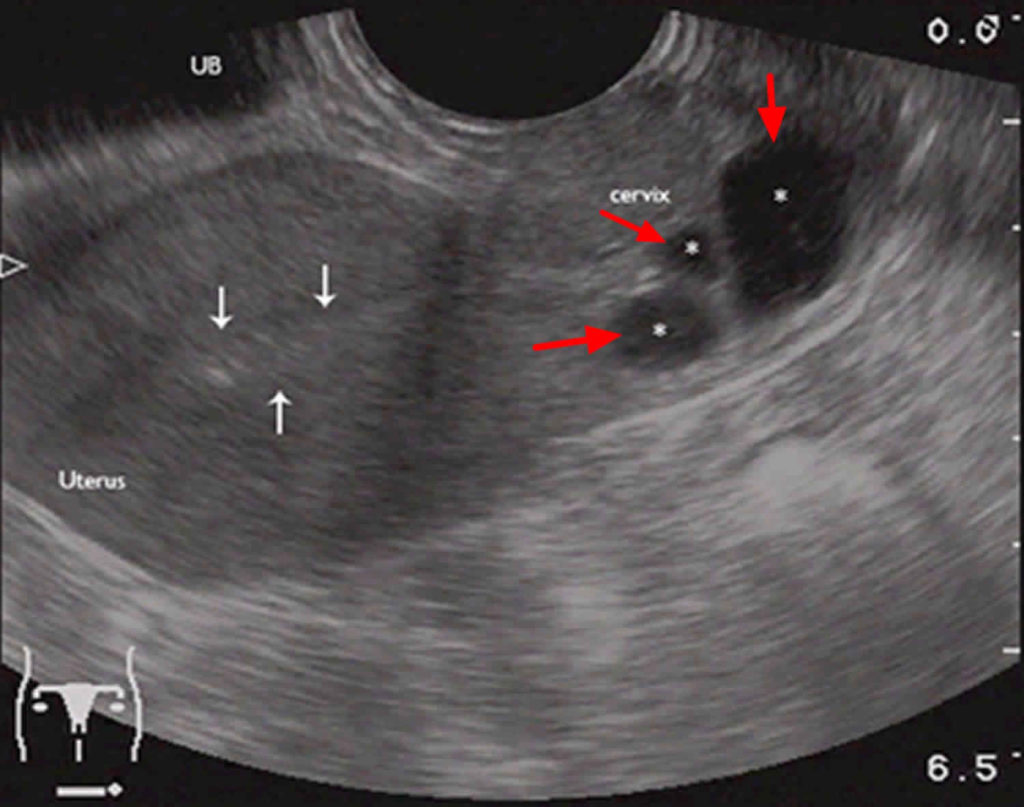

کیست نابوتین که کیست دهانه رحم، کیست احتباس مخاطی یا کیست اپیتلیال نیز نامیده می‌شود، کیست ریزی است که روی سطح دهانه رحم ایجاد می‌شوند. این کیست مملو از مخاطی است که توسط غدد دهانه رحم ترشح می‌شود.

اندازه کیست های نابوتین از چند میلی‌متر تا چهار سانتیمتر متغییر است. این کیست ها صاف هستند و به زنگ سفید یا زرد ظاهر می‌شوند. اما باعث درد، ناراحتی یا علائم دیگر نمی‌شوند؛ بنابراین احتمالا پزشکتان در طول معاینات معمول لگن متوجه بروز یک یا چند کیست در دهانه رحم شما خواهد شد.

کیست های نابوتین خوش خیم هستند و عموما نیاز به درمان ندارند. در موارد نادر این کیست ها ممکن است بزرگ شوند و شکل و اندازه دهانه رحم را تغییر دهند. اگر کیست نابوتین شما حاد باشد می‌تواند معاینه معمول دهانه رحم را دشوار یا غیرممکن کند. در این موارد پزشک ممکن است برداشتن کیست نابوتین را به منظور معاینه دهانه رحم توصیه کند.